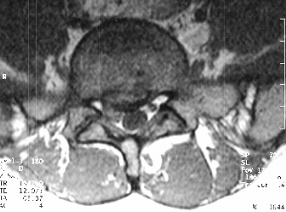

Radiological Evaluation

- plain x-rays normal, with mild spinal curve

- MRI-L5-S1 Right disc herniation with nerve root impingement

- Myleogram reveals nerve root impingement

- Right L5-S1 Disc Herniation